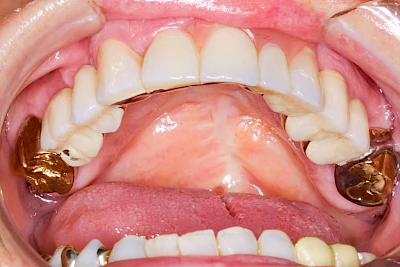

Überbeine im Bereich der Kiefer sind gar nicht so selten. Häufiger im Bereich der Seitenzähne unterhalb des Zahnfleisches, aber auch in der Mitte vom Gaumen. Überbeine haben in dem Sinne keinen Krankheitswert, müssen also nicht operativ entfernt werden, wenn diese nicht stören. Überbeine können ein Anzeichen für Knirschen und Pressen sein.